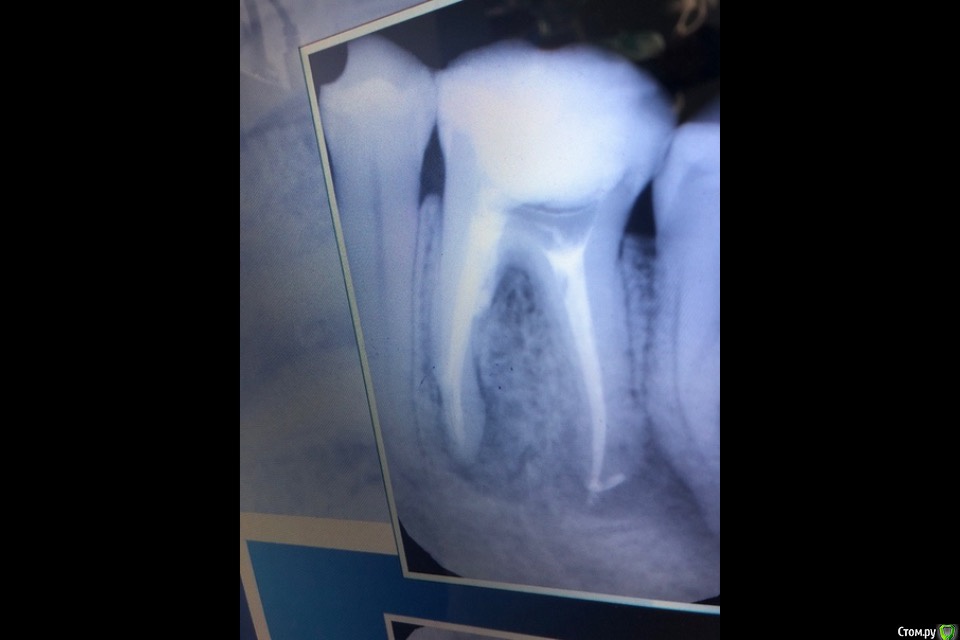

nashe72 Опубликовано 15 сентября, 2018 Поделиться Опубликовано 15 сентября, 2018 (изменено) Здравствуйте.Можно ли спасти этот зуб или только удаление? Боли нет, но постоянно чувствую дискомфорт в его области, пульсацию, "токанье". Также чувствую постоянный запах, думаю от него, так как другие зубы здоровы. Боюсь негативных последствий и очень жалко основной жевательный зуб. [ Изменено 15 сентября, 2018 пользователем nashe72 Ссылка на комментарий

St. Опубликовано 15 сентября, 2018 Поделиться Опубликовано 15 сентября, 2018 В этом зубе присутствует хроническое воспаление за пределами корня. Вероятность успеха лечения достаточно высока, но требует терпения (во-первых перелечивание каналов очень небыстрый и кропотливый процесс, во-вторых результат заживления будет видно не сразу потому что кость очень медленная ткань и чем дефект больше тем медленнее он соответственно заживает) и определенных финансовых вложений. Чтобы сохранить зуб нужно найти доктора который занимается лечением каналов, достать из зуба металлический штифт, старый материал из каналов, продезинфицировать это пространство и заново закрыть новым материалом. Потом этот зуб восстановить коронкой и через 6 и 12 мес делать контрольные снимки смотреть есть ли заживление и как быстро оно идет. 3 Ссылка на комментарий

DmitrySH Опубликовано 29 сентября, 2018 Поделиться Опубликовано 29 сентября, 2018 Сложное и кропотливое лечение. В умелых руках с большой вероятностью успеха. Желательно наличие оптики (микоскопа) у врача, т.к. есть подозрение на наличие фрагмента инструмента в переднем корне Ссылка на комментарий

nashe72 Опубликовано 27 апреля, 2019 Автор Поделиться Опубликовано 27 апреля, 2019 Всем привет.Сделал снимок спустя пол года. Зуб особо не беспокоит, но периодически слегка ноет и опухоль со стороны щеки осталась. Пальцем не прощупывается, языком чувствуется отчетливо.Хотел бы спросить ваше мнение по поводу снимка, стало ли хуже, чем на предыдущих фото? И еще не могу понять, куда делся материал из левого канала? Врач, делающий снимок, не смог дать ответ. На снимке в ноябре, сразу после лечения, канал заполнен, на этом, он полупустой. Это чем то может грозить мне? Ссылка на комментарий